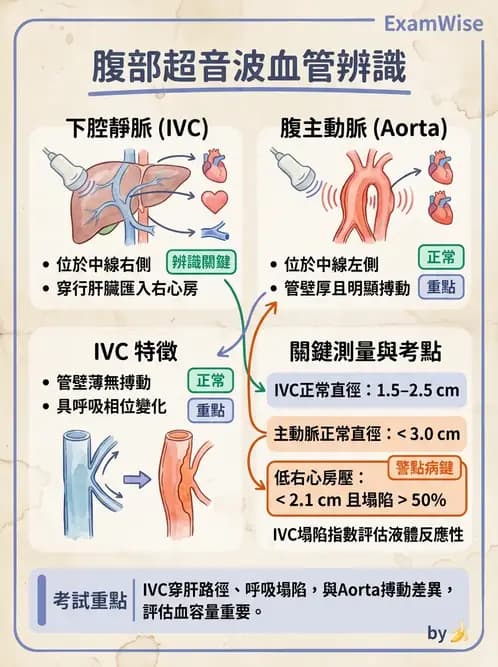

腹部超音波中辨識腹腔主要血管(下腔靜脈、主動脈、上腸系膜動脈、脾靜脈)的解剖位置與超音波特徵,是醫事檢驗師必須熟練的基本技能。本題考核對「下腔靜脈(inferior vena cava, IVC)」的超音波影像辨識能力。

本題超音波圖像為腹部縱切面(長軸切面)影像,顯示肝臟實質(灰色均勻回音區)及其下方的腹腔結構。白色箭頭指向位於影像中央偏下的一條管狀、無回音(anechoic)結構,具有以下特徵:

- 位置:位於脊椎的右前方,穿行於肝臟實質之中(intrahepatic segment),屬於中線偏右側

- 管壁:壁薄而不明顯,不像主動脈(aorta)具有厚實的高回音管壁

- 管腔:無回音(anechoic),充滿液體

- 走向:縱向延伸,可見其向頭側(cranially)匯入右心房(right atrium)的走向特徵

- 可壓縮性:靜脈管壁較動脈薄,超音波探頭輕壓時可見受壓塌陷(若有呼吸相位變化則更具診斷意義)

這些特徵高度符合下腔靜脈(IVC)的典型超音波表現:薄壁、無回音、位於中線右側、穿行肝臟並匯入右心房。